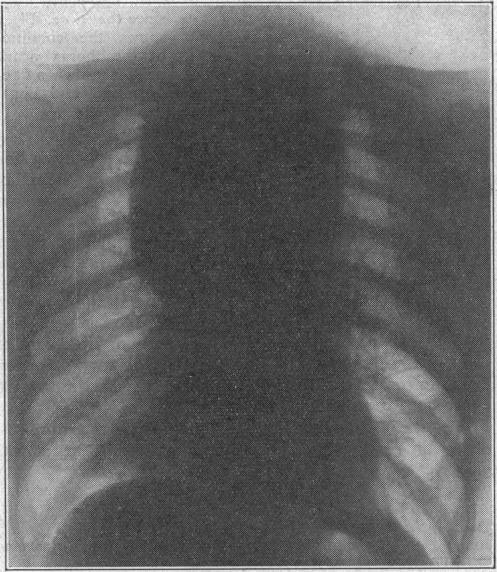

Thyroid Surgery, with a Contribution on Intrathoracic Goitre.

Br Med J. 1950 Mar 18;1(4654):621-6. doi: 10.1136/bmj.1.4654.621.